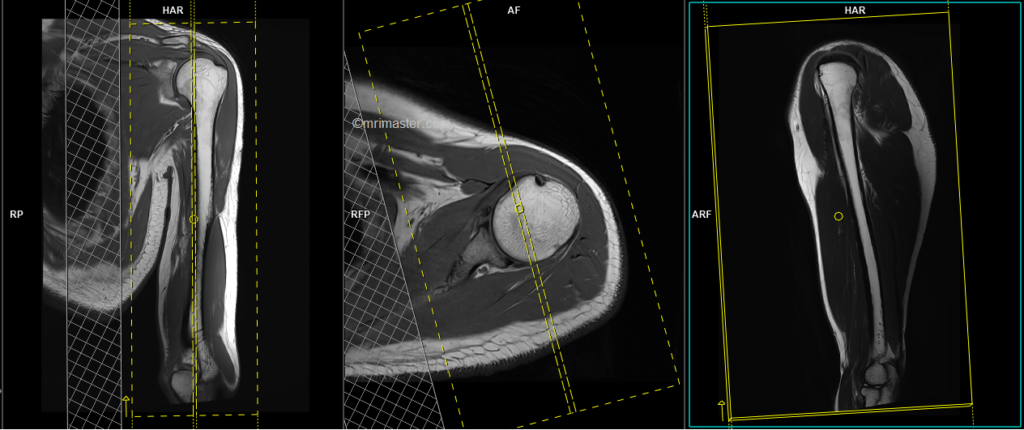

T2 tse sagittal 3mm

Plan the sagittal slices on the axial plane and angle the planning block perpendicular to the scapular blade. Check the planning block in the other two planes. Use an appropriate angle in the coronal plane (parallel to the humerus). The slices must sufficiently cover the entire upper arm from the medial to lateral aspect. The field of view (FOV) should be large enough to encompass both the shoulder and elbow joints. To reduce artifacts from breathing and arterial pulsations, consider adding saturation bands over the chest. For the phase direction, you can choose either anterior to posterior or head to feet. A minimum oversampling of 100% is recommended to avoid wrap-around artifacts.

Parameters

TR 4000-5000 | TE 110 | FLIP 130 | NEX 2 | SLICE 5MM | MATRIX 384X384 | FOV 350-400 | PHASE A>P | GAP 10% | FATSAT Off |